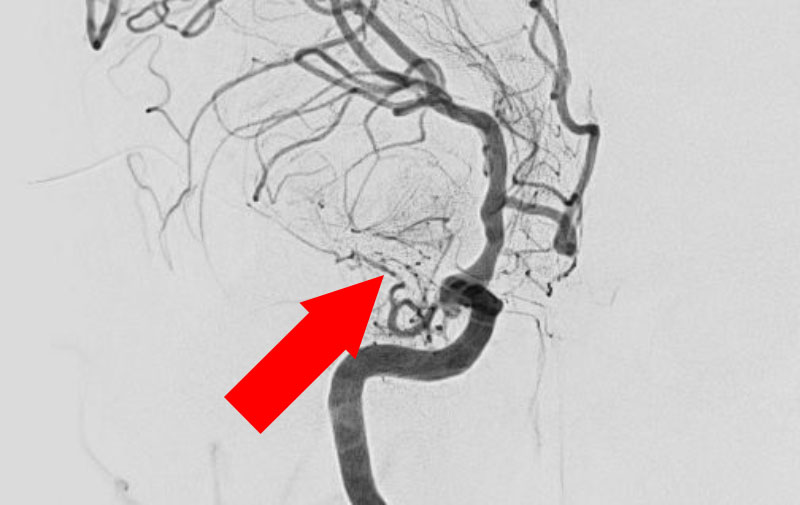

No.622 手術前

No.622 手術中

No.622 手術後